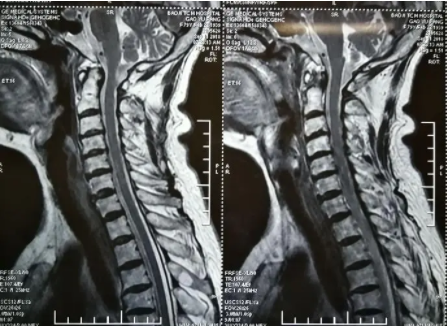

来到医院后,医生先给我进行了一部分检查,通过按压我的颈部肌肉等方式,我明显感觉到颈背部的肌肉按起来很头痛,还伴有太阳穴按压疼痛。然后,医生给我开了个X光检查,拍了颈椎的位置。最后检查结果显示,确实是颈椎病,和从前差不多,是颈椎曲度变直了。不过从前一直没有过这么严重的症状表现,以前只是偶然会有些脖子疼,这次头晕恶心持续了很久。